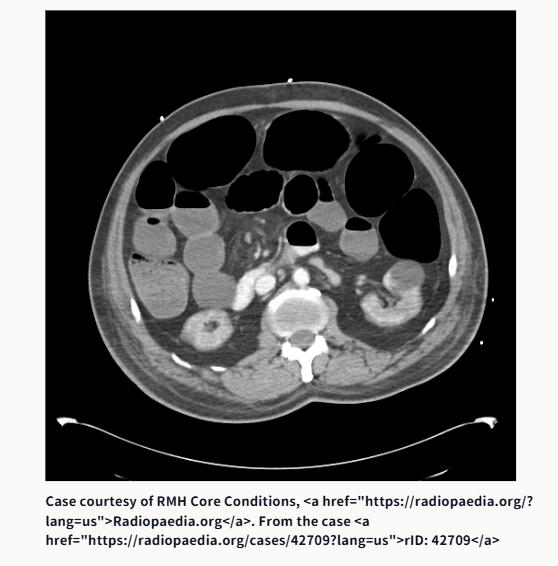

③腸閉塞です。原因は何でしょうか?

③腸閉塞の原因は、鼠径ヘルニア嵌頓です